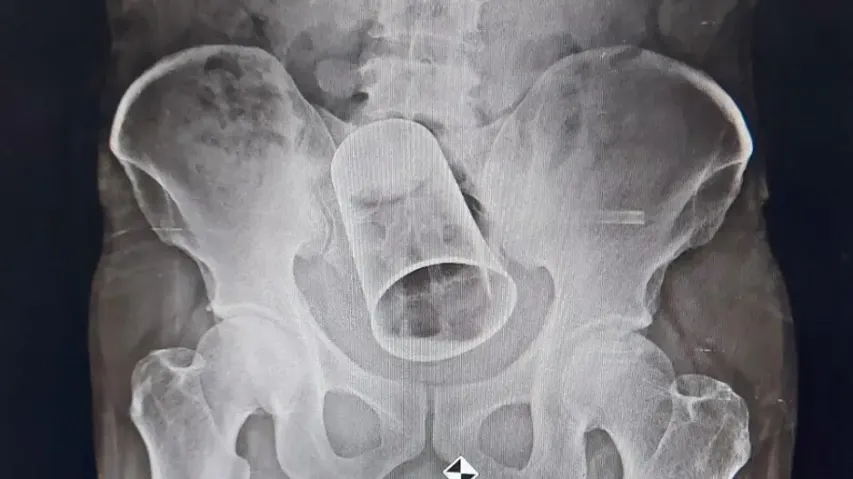

Steel glass removed from patient's intestine at MKCG hospital in Berhampur